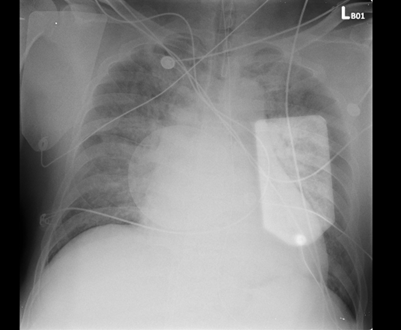

A 60-year-old man with poorly controlled hypertension and a history of cigarette smoking suffered a witnessed out-of-hospital cardiac arrest. The initial rhythm was ventricular fibrillation requiring CPR and multiple defibrillations, with ROSC after ~40 minutes. On arrival, he was intubated and in cardiogenic shock with pulmonary edema. He was stabilized with VA-ECMO, IABP, and mechanical ventilation before coronary angiography.

Relevant Test Results Prior to Catheterization

ECG showed sinus rhythm with ST-segment elevation in V1–V3 and aVL, consistent with anterior STEMI. Brain CT excluded intracranial hemorrhage. Chest CT ruled out aortic pathology but revealed diffuse ground-glass opacities suggesting pulmonary edema. Echocardiography showed severe LV dysfunction with EF 18% and diffuse hypokinesis. Cardiac enzymes were markedly elevated.